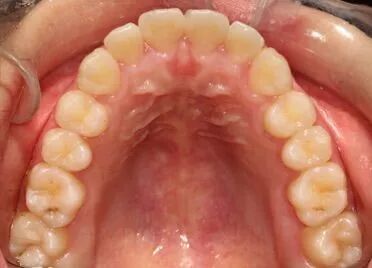

做过正畸的小伙伴们请来回答一个问题~ 矫治结束、摘下牙套之后 最怕的是什么?? 在这里,小编要分享一个正畸小伙伴的“血泪史” 大家引以为戒啊引以为戒!!! 经过3年的辛苦矫正,牙齿终于脱胎换骨~~一口整齐漂亮的小白牙,让我高兴了好一下下~~ 可是!但是!!可但是!!!刚拆了牙套才一年…牙齿就又回去了,又变得不整齐了… 呜呜~奶油冰激凌也弥补不了我的伤心~~我的小白牙为什么会这样?到底是为什么呢? 有图有真相 这是刚拆掉牙套时 这是摘牙套一年之后~~ OMG!!!为什么!! 我去找我的牙医~要去问问他! 医森认真的给我分析了原因.....恍然大悟! 01 牙周及牙龈纤维重建 牙齿经矫治移动后,被拉伸或压缩的牙龈及牙周膜纤维的张力尚未建立新的平衡,牙齿的位置不稳定,容易复发。尤其是牙槽嵴上纤维与横隔纤维的改建非常缓慢,所产生的张力容易使移动的牙再恢复原错位状态。此外,牙槽骨由过渡性骨改建正常牙槽骨也需要一定时间。 02 口周肌力的影响 治疗结束后,由于牙齿牙弓与颌骨的位置发生了改变肌动力平衡也因此有了变化,由于错牙合畸形形态学的改变往往先于功能和肌动力的改建,即原有的动力平衡对矫治后的牙齿、牙弓及颌骨位置会产生一定的负面影响医|学教|育网搜集整理,使之呈现不稳定状态。 03 咬合平衡未完全建立 在矫治过程中,由于改变了牙、牙弓和颌骨位置关系,因而破坏了原有已习惯的异常关系。新建的牙合关系还未达到颌面恰好吻合,与牙尖斜面的接触关系,还必须经过不断调整,在调整过程中,有复发的倾向。 04 不良习惯的影响 口腔不良习惯是造成错颌畸形的一个重要原因,若在正畸治疗结束时,仍未纠正口腔不良习惯,极容易导致错颌畸形的复发,比如异常吞咽、伸舌习惯导致开颌畸形复发 05 口腔正畸后需保持时间 戴用保持器的期限没有具体规定,一般应与错颌病因、错颌类型等因素有关。一般人认为保持时间为2年左右。保持时间越长,效果越稳定。 除了上述原因外,还可能与长智齿、不良习惯 ,不利的生长发育等有关…… 温馨提示 为提高居民口腔保健知识,增强口腔保健意识,为各单位团体、中小学校、社区组织提供免费口腔健康讲座、口腔健康义诊等公益服务。 如有需要请联系宣传科:18806332046 (费先生) 地址:望海路与正阳路交汇处(日照市中医医院东邻) 咨询热线:0633—2222226 关注下方二维码 了解更多内容经过医生的分析,我终于明白了原因……